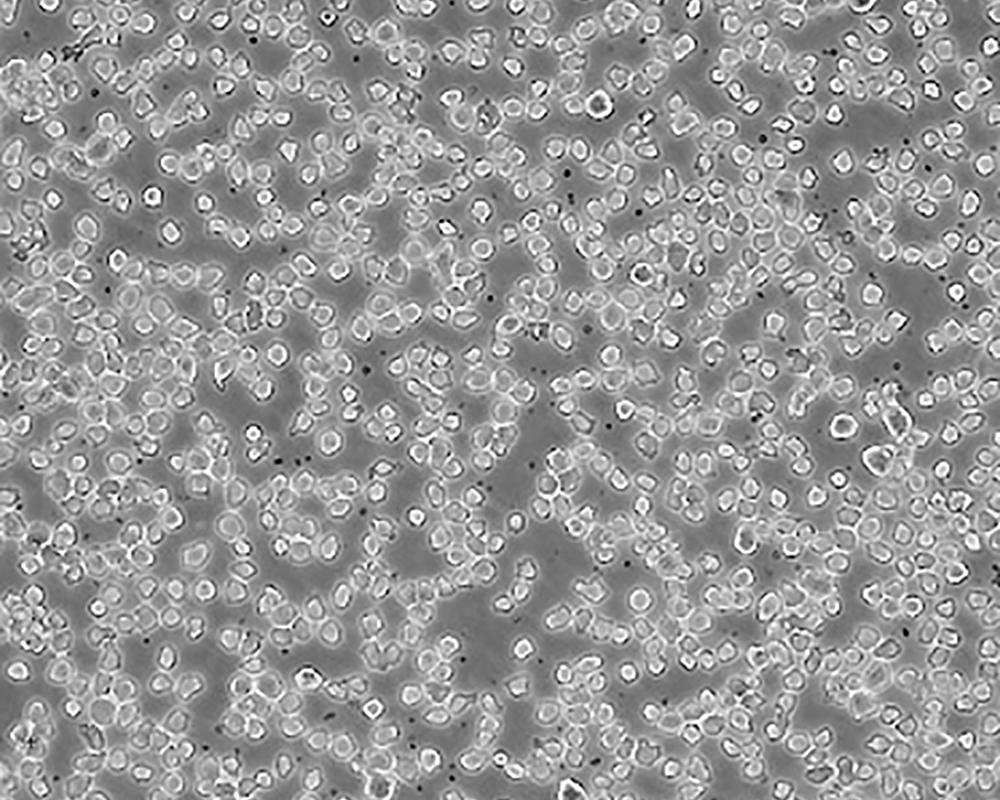

THP-1

中文名稱 人單核細胞白血病

組織來源 急性單核細胞白血病;男性

生長特性 suspension

形態特征 monocyte

細胞描述 該細胞從一名1歲的患有急性單核細胞性白血病的男孩的外周血中分離建立。該細胞可以吞噬乳膠顆粒和激活的紅細胞,細胞膜和胞漿內均沒有免疫球蛋白,表達C3R和FcR;可受佛波酯TPA誘導向單核系方向分化;可作為轉染宿主。